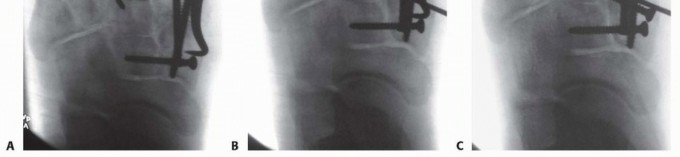

Initial radiographic evaluation consists of non-weight-bearing anteroposterior (AP), oblique, and lateral views of the foot, which, depending on the extent of intra-articular displacement, may provide sufficient diagnostic information (

FIG 3A-C

).

Fluoroscopic stress views may be helpful in more subtle injuries; however, these studies are painful and generally require anesthesia.

We therefore prefer weight-bearing radiographs of the foot for more subtle injuries (

FIG 3D-H

); comparison weight-bearing radiographs of the contralateral foot may also be obtained where necessary.

The weight-bearing AP view of the foot will demonstrate intra-articular displacement through the first and second tarsometatarsal joints (so-called Lisfranc joint), intercuneiform joint, and naviculocuneiform joint; fractures through the first and second metatarsal bases, medial and middle cuneiforms, and proximal extension into the navicular; and the extent of columnar shortening or asymmetry.

The medial border of the second metatarsal should align with the medial border of the middle cuneiform (

FIG 3D

The oblique view will reveal intra-articular displacement through the third, fourth, and fifth tarsometatarsal joints and fractures of the third, fourth, and fifth metatarsal bases, lateral cuneiform, and cuboid.

The medial borders of the third and fourth metatarsals should align with the medial borders of the lateral cuneiform and cuboid, respectively (

FIG 3E

The lateral view may reveal dorsal-plantar displacement of fractures or dislocations as well as any flattening of the medial longitudinal arch, thereby reflecting the status of the weight-bearing medial column and first ray (

FIG 3F

FIG 3

• Non-weight-bearing AP (

A

), oblique (

B

), and lateral (

C

) radiographs of grossly unstable, purely ligamentous, Lisfranc dislocation involving all five tarsometatarsal articulations. Marked lateral subluxation through all five tarsometatarsal joints is evident on the AP and oblique views, and significant dorsal displacement is evident on the lateral view. Weight-bearing lateral (

D

), AP (

E

), and oblique (

F

), and non-weight-bearing (

G

) and oblique (

H

) radiographs of more subtle Lisfranc injury. Lateral and plantar subluxation (

black arrows

) is evident on the weight-bearing radiographs, and displacement of normal radiographic landmarks (

black lines

) confirms injury.